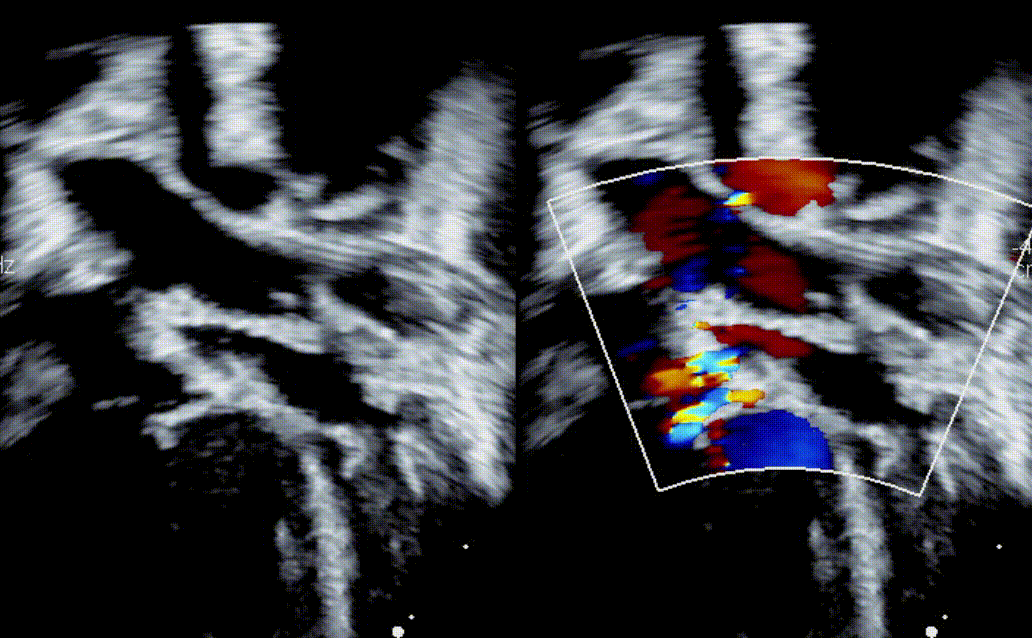

What defect is shown?

What direction is the flow?

What is a bidirectional VSD